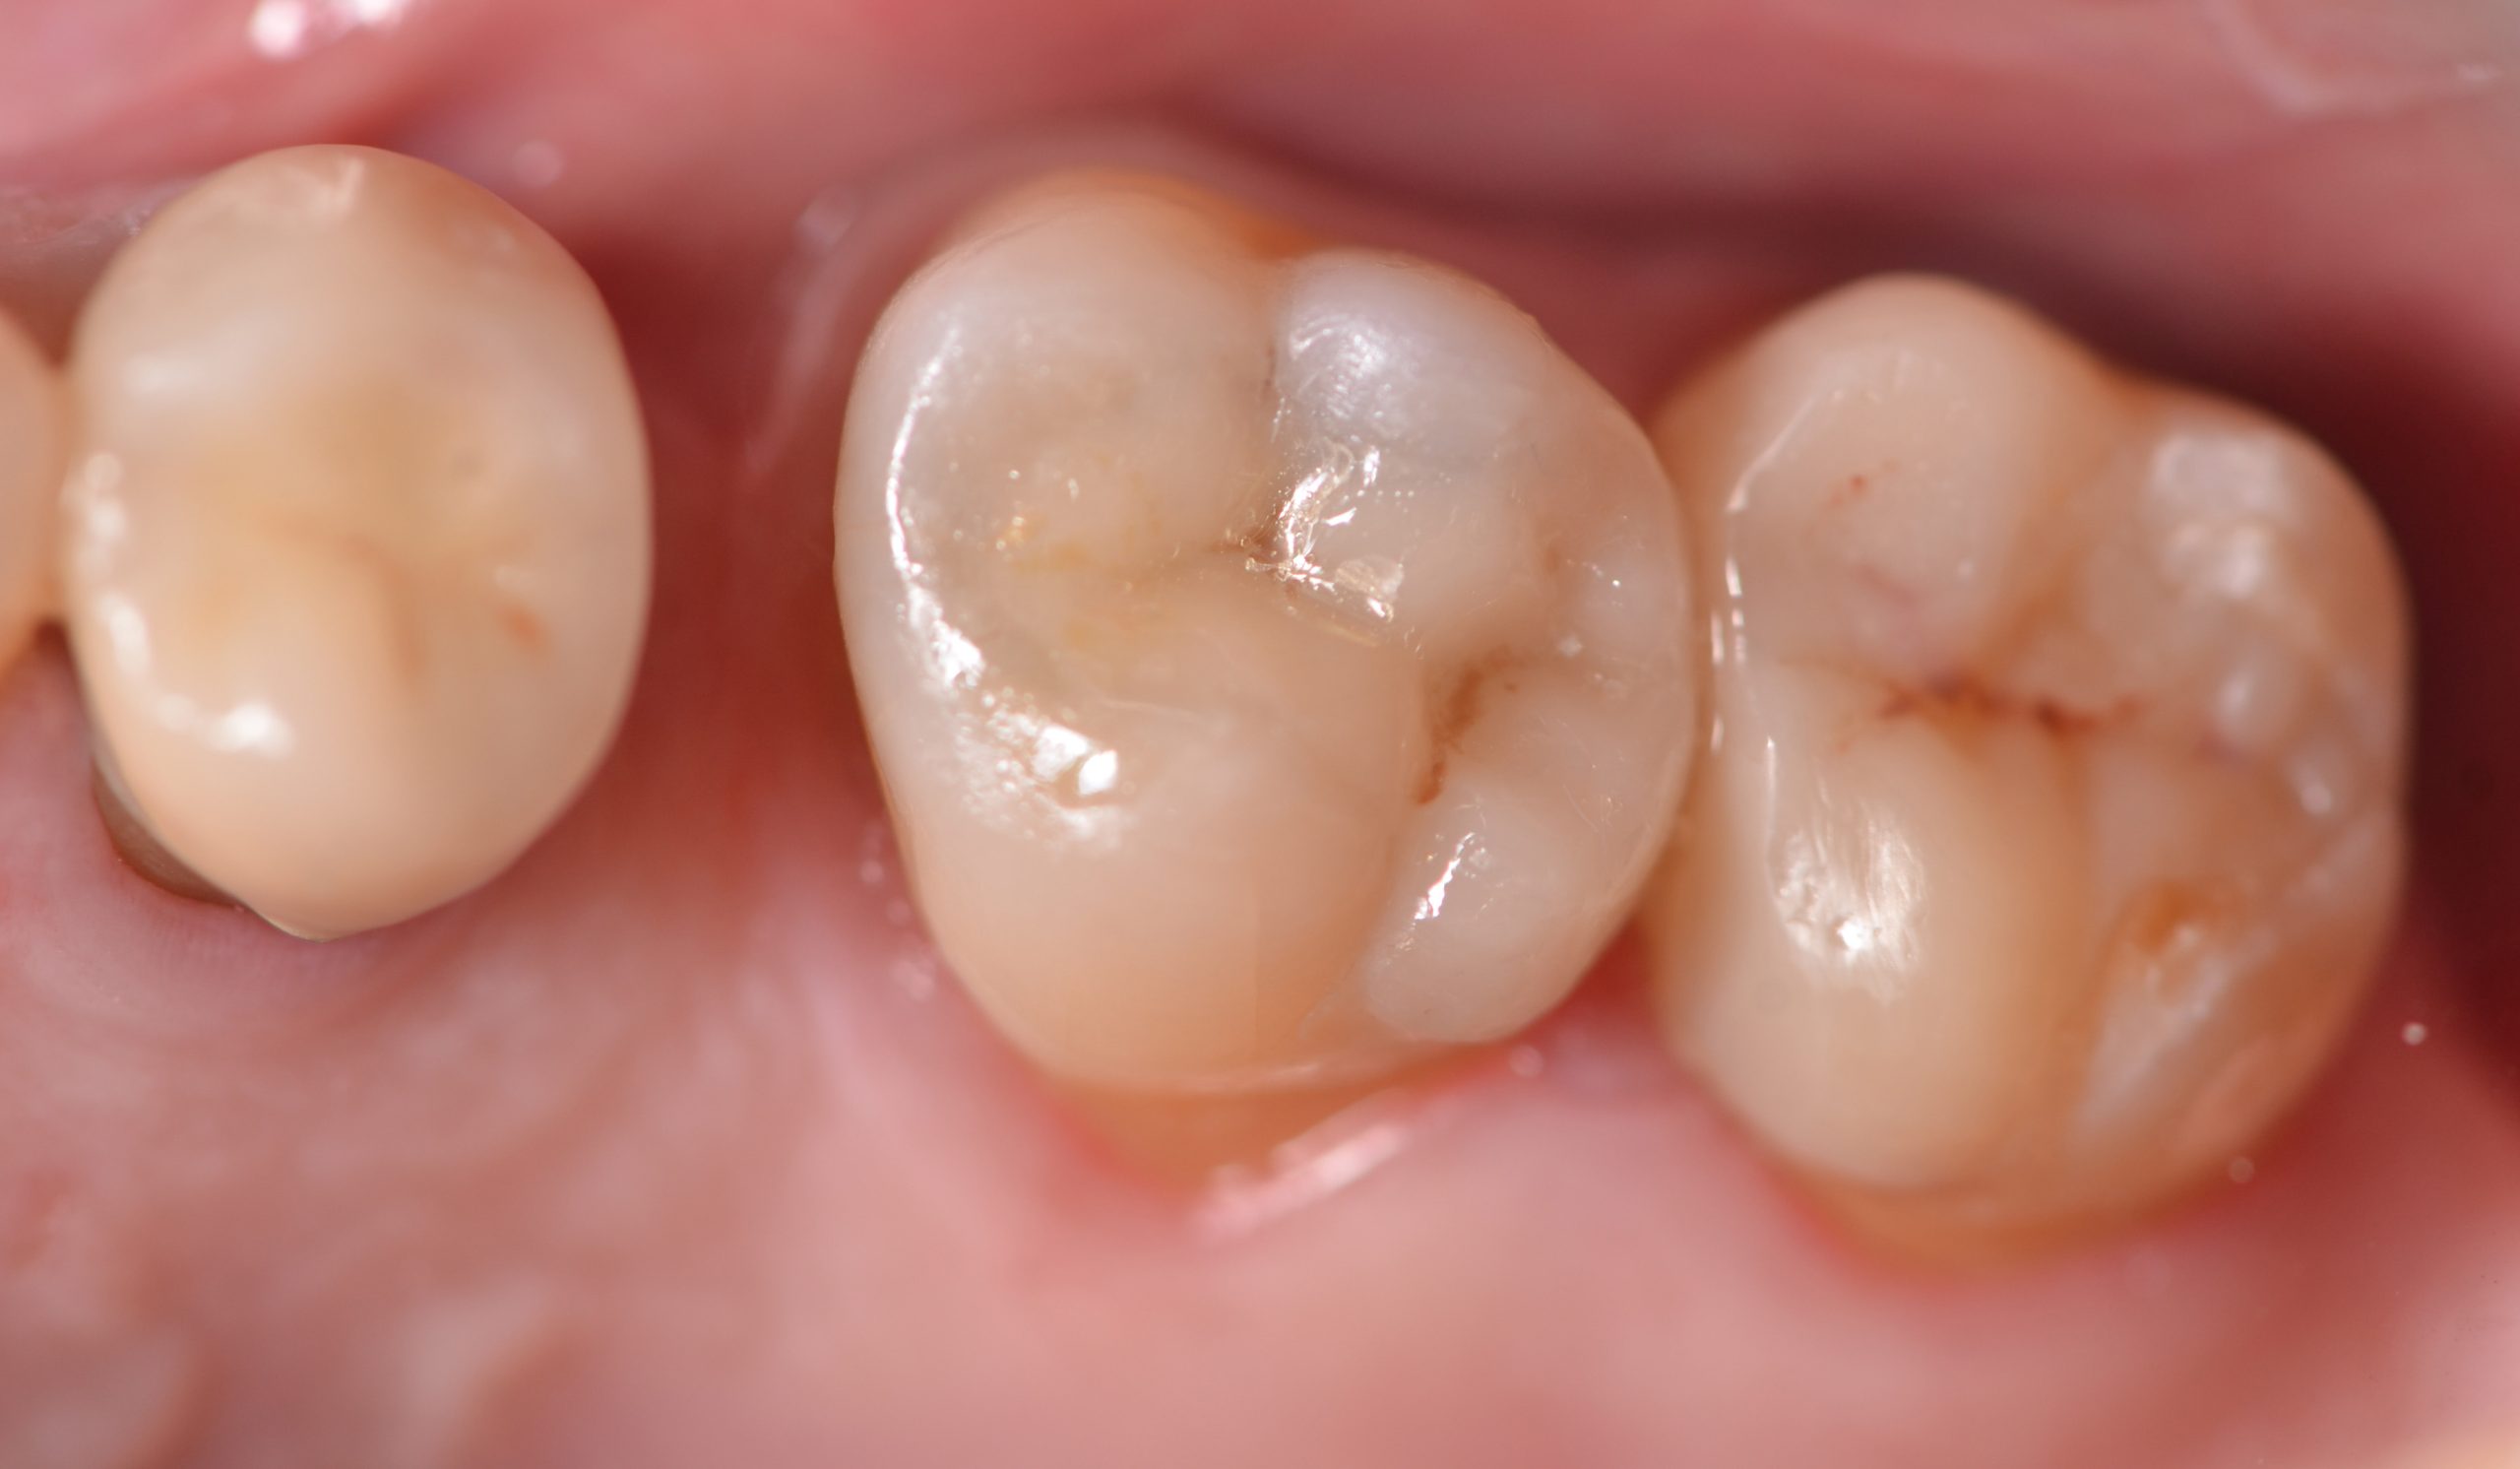

Rifinitura e lucidatura dei restauri

Dopo la rimozione della diga di gomma, per le zone di contatto si procede a rifiniture interprossimali con strisce abrasive. Concluso il controllo occlusale, per il molaggio selettivo dei precontatti si utilizza una fresa a pallina in carburo di tungsteno. Seguono quindi rifinitura e lucidatura con gommini abrasivi diamantati. Alcune superfici ruvide dell’overlay vengono rifinite e lucidate con l’ausilio di dischetti abrasivi a grana fine e di gommini. Con i dischi in feltro si passa alla lucidatura a specchio impiegando una pasta non abrasiva all’ossido di cerio. Dopo 15 giorni, si eseguono controllo radiografico e verifica del restauro eseguito (Figure 16-18). La Tabella 1 riassume il protocollo clinico utilizzato in questo case report.